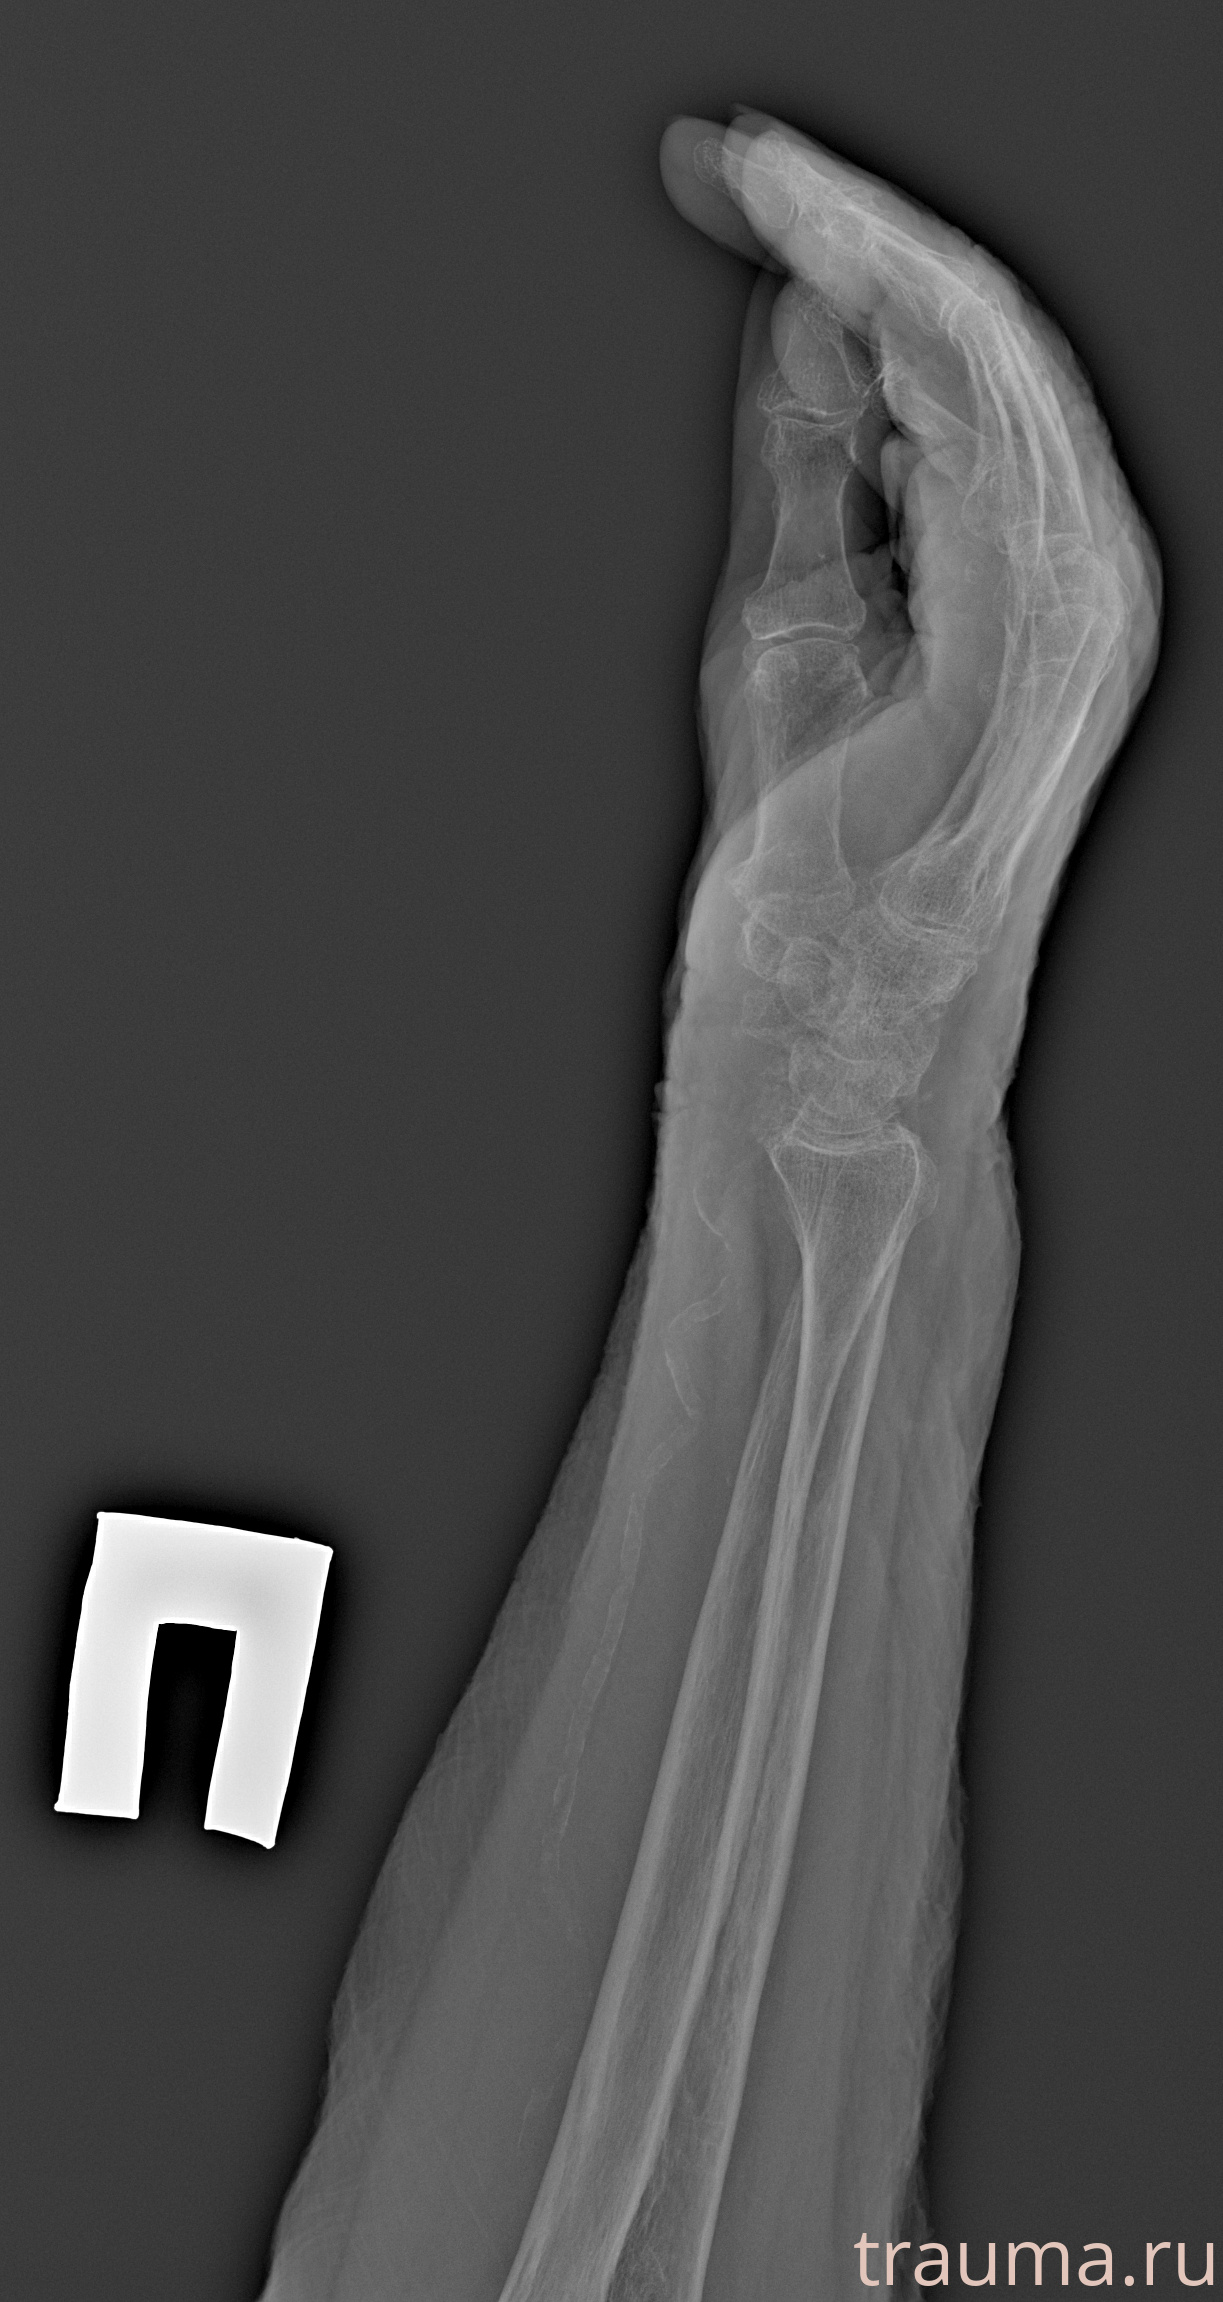

Рентген на дому: по вашему адресу приезжает врач-рентгенолог, травматолог-ортопед с мобильным рентгеновским аппаратом, проводит диагностику травмы или заболевания, делает необходимые рентгенограммы, дает рекомендации по дальнейшему лечению. Получить качественные снимки в домашних условиях возможно благодаря уникальной методике, разработанной МосРентген Центром для института  Склифосовского